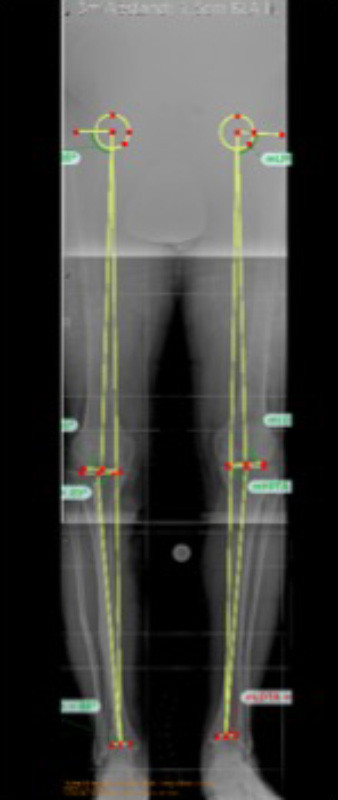

Ausmessen der Beinachse

Ausmessen der Beinachse zur Planung einer operativen Korrektur bei X-Beinstellung durch einen fehlverheilten Bruch des Schienbeinkopfes